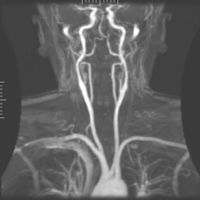

تصوير الأوعية بالرنين المغناطيسي